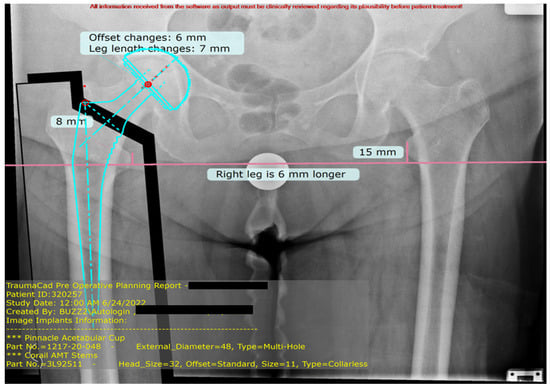

The Role of Osteoporosis in Digital Templating Accuracy for Primary Cementless Total Hip Arthroplasty: A Prospective Study

by Michele Mercurio, Erminia Cofano, Paola Morabito, Lucrezia Moggio, Filippo Familiari, Olimpio Galasso and Giorgio Gasparini

Appl. Sci. 2025, 15(20), 11192; https://doi.org/10.3390/app152011192 - 19 Oct 2025

Background: Total hip arthroplasty (THA) is one of the most effective treatments for end-stage hip joint disease. Two-dimensional (2D) templating represents the most widely used method for preoperative planning in clinical practice. Patient characteristics and comorbidities may further influence and complicate radiographic templating. The present study aimed to evaluate the role of comorbidities in influencing the accuracy of 2D digital preoperative planning in primary cementless THA. Methods: In this prospective observational study, all patients underwent standardized anteroposterior pelvic radiographs, and a digital templating was performed using digital software. Patient demographic characteristics, such as age, sex, BMI, and comorbidities, were extracted and all the patients were divided into matched and mismatched group for the femoral stem, femoral head, and acetabular cup. Results: The final sample consisted of 71 patients with 44 (62%) female and 27 (38%) male patients, averaging 69.8 ± 10.6 years at surgery. For the femoral stem, no statistically significant differences were found between the two groups according to comorbidities. For the femoral head, 12.5% and 50% of the patients had osteoporosis in the matched group and mismatched group, respectively (p-value = 0.002). For the acetabular cup, 18.4% and 40.9% of the patients had osteoporosis in the matched and mismatched groups, respectively (p-value = 0.043). Conclusions: Two-dimensional digital templating is a reliable technique for preoperative planning in primary cementless THA. Osteoporosis significantly influences templating accuracy, often resulting in component oversizing. Full article